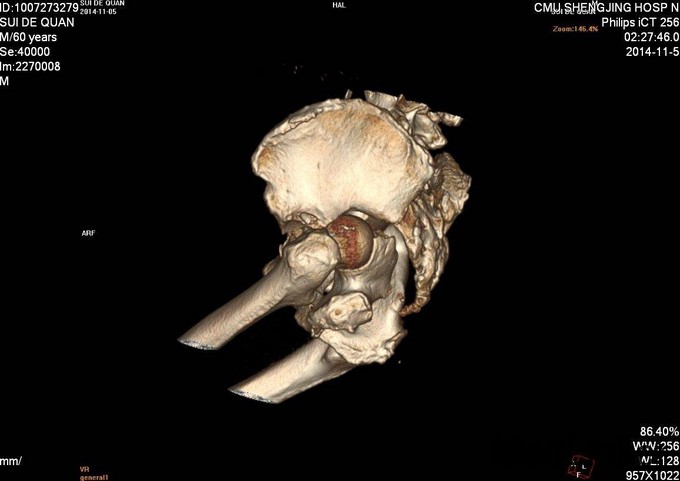

1.患者老年男性,以“车祸左髋部疼痛活动受限3天”为主诉入院。 2.现病史:患者自述于2014-11-04日晚下午7点发生机动车肇事,伤后患者急救车送往孤山二院,诊断为左髋臼骨折,当地医院未经任何治疗。急来中国医科大学附属盛京医院第五骨科创伤骨科治疗。我科以“左髋臼骨折”为主要诊断收入院。今来我院就诊,患者病来一般状态可,生命体征平稳,无发烧无发热,饮食睡眠可。

专科查体:患者平车入病房,左腿内收内旋屈曲畸形,左髋部压痛(+),叩击痛(+),骨盆分离试验阳性,活动受限,双下肢感觉未见异常,活动可,双侧足背动脉搏动可触及,双侧足趾活动灵活。

入院后急诊行左髋关节脱位复位术,左胫骨结节骨骼牵引术。术后牵引7公斤,完善相关检查后,全麻下行左髋臼骨折切开复位内固定术。术后患者生命体征平稳,卧床。术后14天拆线后出院,回当地医院继续治疗。